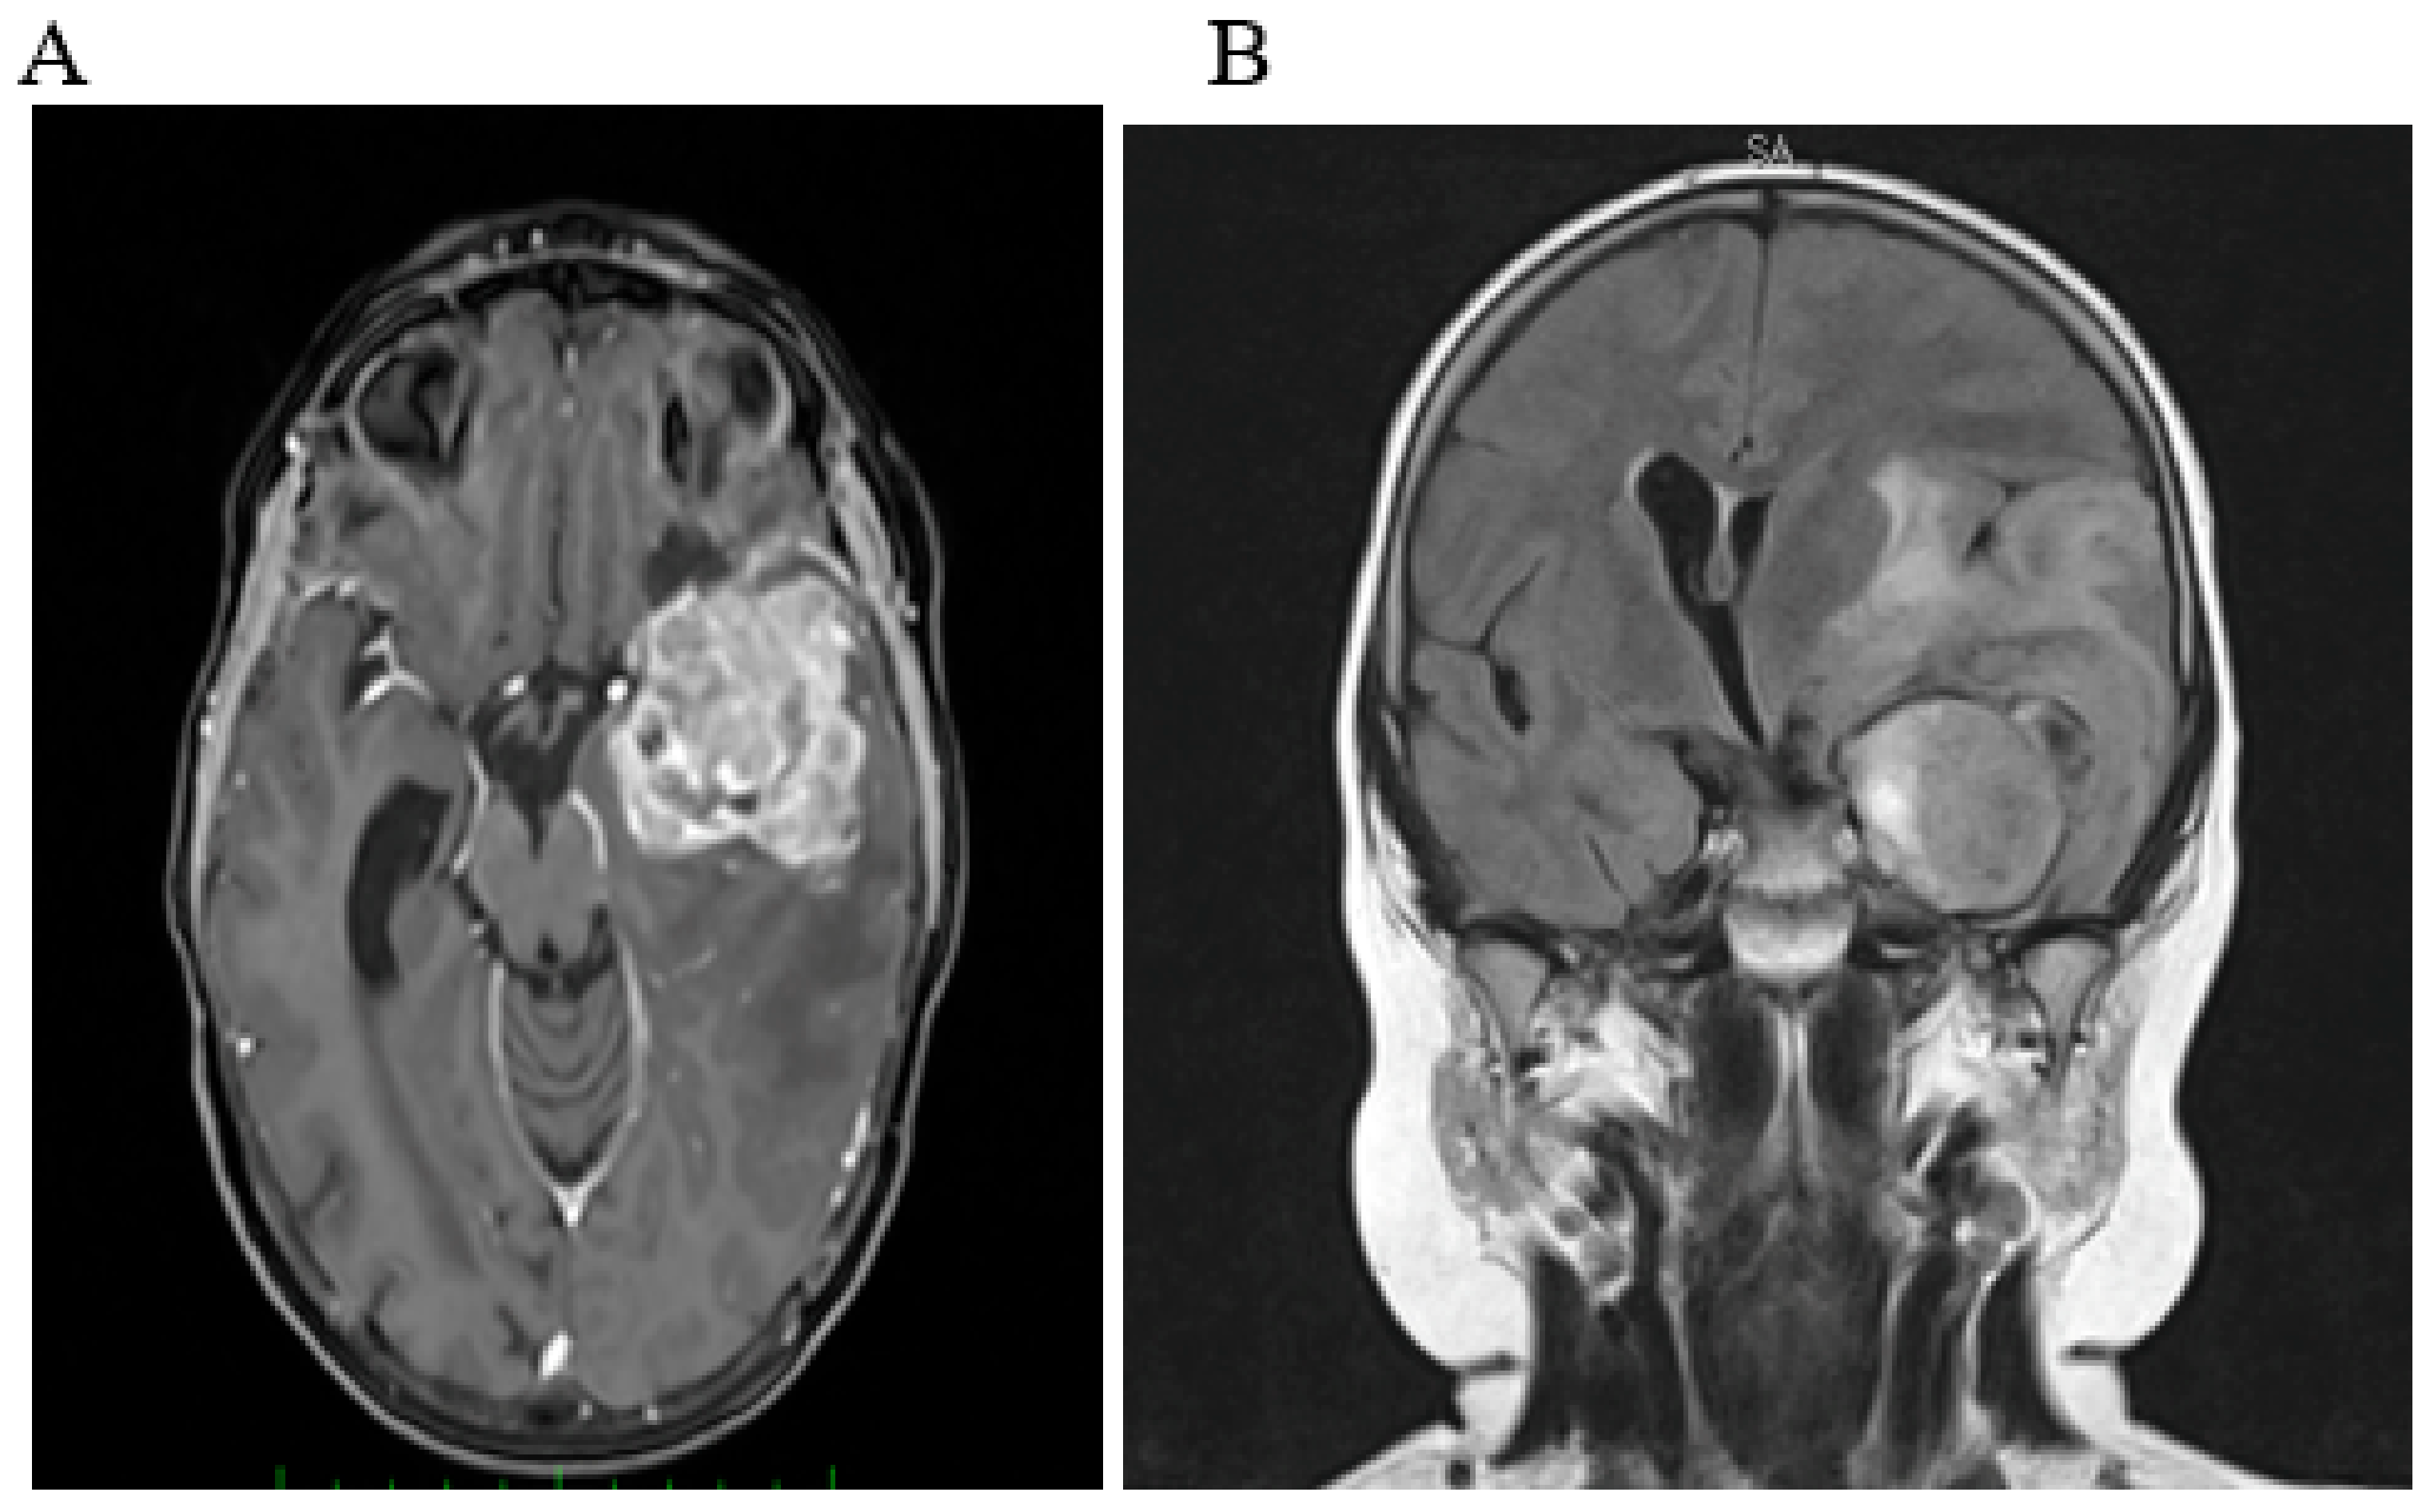

2.1. Case 1

- Berlanga, P.; Pasqualini, C.; Pötschger, U.; Sangüesa, C.; Castellani, M.R.; Cañete, A.; Luksch, R.; Elliot, M.; Schreier, G.; Kropf, M.; et al. Central nervous system relapse in high-risk stage 4 neuroblastoma: The HR-NBL1/SIOPEN trial experience. Eur. J. Cancer 2021, 144, 1–8. [Google Scholar] [CrossRef]

- DuBois, S.G.; Kalika, Y.; Lukens, J.N.; Brodeur, G.M.; Seeger, R.C.; Atkinson, J.B.; Haase, G.M.; Black, C.T.; Perez, C.; Shimada, H.; et al. Metastatic sites in stage IV and IVS neuroblastoma correlate with age, tumor biology, and survival. J. Pediatric Hematol. Oncol. 1999, 21, 181–189. [Google Scholar] [CrossRef]

- Stefanowicz, J.; Iżycka-Świeszewska, E.; Szurowska, E.; Bień, E.; Szarszewski, A.; Liberek, A.; Stempniewicz, M.; Kloc, W.; Adamkiewicz-Drożyńska, E. Brain metastases in paediatric patients: Characteristics of a patient series and review of the literature. Folia Neuropathol. 2011, 49, 271–281. [Google Scholar]

- Wiens, A.L.; Hattab, E.M. The pathological spectrum of solid CNS metastases in the pediatric population. J. Neurosurg. Pediatr. 2014, 14, 129–135. [Google Scholar] [CrossRef]

- Matthay, K.K.; Brisse, H.; Couanet, D.; Couturier, J.; Bénard, J.; Mosseri, V.; Edeline, V.; Lumbroso, J.; Valteau-Couanet, D.; Michon, J.; et al. Central nervous system metastases in neuroblastoma: Radiologic, clinical, and biologic features in 23 patients. Cancer 2003, 98, 155–165. [Google Scholar] [CrossRef] [PubMed]